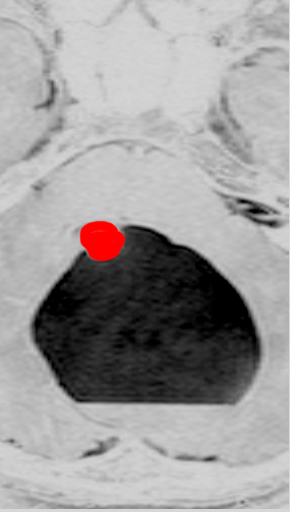

思春期の女の子にできた小脳腫瘍です。とても大きく見えますがほとんどが水たまり(のう胞といいます)。第4脳室が腫瘍で圧迫されて閉塞性水頭症になりました。のう胞の中に出血がありますが毛様細胞性星細胞腫では腫瘍内出血をしばしば見ます。右の写真で脳室が大きくなっています。こんなに大きいのに小脳症状は全くなくて,頭痛と嘔吐が症状でした。

赤で塗ったところだけが毛様細胞性星細胞腫です。これを取れば治ります。簡単な手術ですし後遺症も残りません。